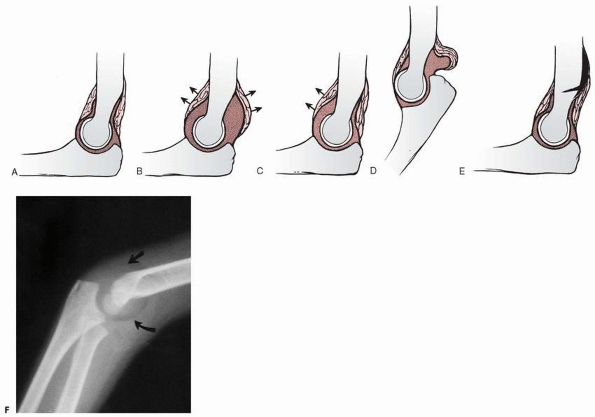

major structures of the elbow. Displacement of any of the fat pads can

indicate an occult fracture. The first two areas are the fat pads that

overlie the capsule in the coronoid fossa anteriorly and the olecranon

fossa posteriorly. Displacement of either or both of these fat pads is

usually referred to as the classic elbow fat pad sign. A third accumulation of fat overlies the supinator muscle as it wraps around the proximal radius.

fossa is deep, the fat pad here is totally contained within the fossa.

It is not visible on a normal lateral radiograph of the elbow flexed to

90 degrees (Fig. 13-18A).

with an occult intra-articular fracture, a spontaneously reduced

dislocation, or even an infection, can cause the dorsal or olecranon

fat pad to be visible.48

Because the coronoid fossa is shallow, the fat pad in this area

projects anterior to the bony margins and can be seen normally as a

triangular radiolucency anterior to the distal humerus. Although

displacement of the classic elbow fat pads is a reliable indication of

an intra-articular effusion, there may be instances in which only one

of the fat pads is displaced. Brodeur et al.9 and Kohn31

have shown that the coronoid fat pad is more sensitive to small

effusions than the olecranon fat pad. It can be displaced without a

coexistent displacement of the olecranon fat pad (Fig. 13-18C).

FIGURE 13-18 Radiographic variations of the elbow fat pads. A. Normal relationships of the two fat pads. B. Displacement of both fat pads (arrows) with an intra-articular effusion. C. In some cases, the effusion may displace only the anterior fat pad (arrows). D. In extension, the posterior fat pad is normally displaced by the olecranon. E. An extra-articular fracture may lift the distal periosteum and displace the proximal portion of the posterior fat pad. F. A radiograph showing displacement of both fat pads (arrows)

from an intra-articular effusion. (Modified and reprinted with permission from Murphy WA, Siegel MJ. Elbow fat pads with new signs and extended differential diagnosis. Radiology 1977; 124:656-659.) |

described other variations of classic fat pad displacement. If the

elbow is extended, the fat pad is normally displaced from the olecranon

fossa by the olecranon (Fig. 13-18D). Distal

humeral fractures may cause subperiosteal bleeding and may lift the

proximal portion of the olecranon fat pad without the presence of an

effusion (Fig. 13-18E). These false-negative

and falsepositive findings must be kept in mind when interpreting the

presence or absence of a fat pad with an elbow injury.